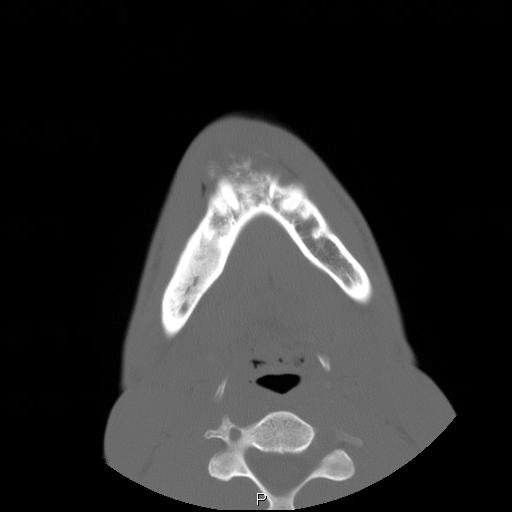

Clinical information The patient was a 23 year-old man who went to see the dentist because of dull pain, swelling of the chin,  and loosened lower front teeth. He was referred to this hospital after initial examination. A CT scan was performed and and a biopsy was taken. Representative images are presented here. Panel D is a sagittal reconstruction from axial CT scans. A resection was subsequently performed.

CT scan: On the CT scan images (Panel A, B, C, and D), two lesions are present.  There is a lesion at the mental protuberance that appears to have penetrated the cortex and invaded into the soft tissue. The patchy hyperdensity strongly suggests that this lesion has mineralize elements ( in Panel B). The border of the lesions in the mandible is poorly defined. The penetration of the bone and extension into the soft tissue is best appreciated in the sagittal reconstruction in (Panel D). These features are highly suggestive of a malignant neoplasm that originates from the bone with extension into surrounding soft tissue. The hyperdensity of the mass suggests bone formation and the radiologic features are suggestive of an osteosarcoma. In the right body of the mandible, there is a diffusely expansile lesion  with some hazy hyerdensity (Ú in Panel B). The cortical bone overlying this lesion is intact. This lesion may represent extension of the osteosarcoma into the body. However, it may also represent a co-existing fibrous dysplasia.